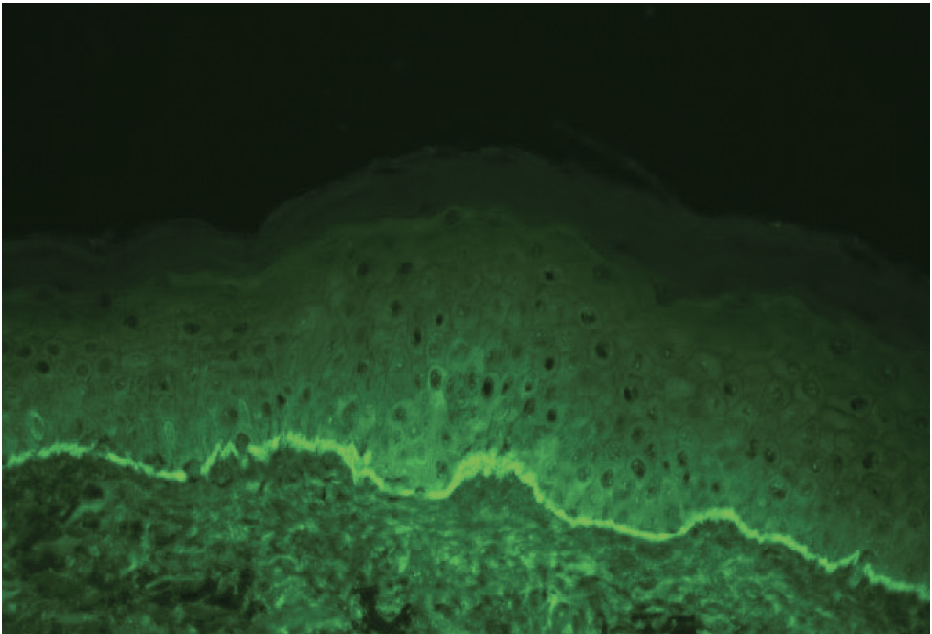

The patient’s diagnosis of localized BP was confirmed with H&E stain and DIF histopathology, which revealed eosinophil-rich subepidermal blistering and a linear deposition of IgG and C3 along the basement membrane, respectively (Figures 2–4). Serology was also positive for BP180 antibodies. The patient was prescribed topical clobetasol propionate 5% cream, which led to significant improvement in his pruritus and bullae. He denied systemic therapy and is being closely monitored. To date, the patient has not experienced any recurrence or disease progression.

Histopathology will reveal a clean split at the dermoepidermal junction and formation of a subepidermal blister with eosinophils. Direct immunofluorescence (DIF) is considered the gold standard for diagnosis and will reveal linear IgG and/or C3 at the basement membrane in nearly 100% of cases. Serologic workup will be positive for autoantibodies against BP180 or BP230.2

DIF is necessary to differentiate BP from other vesiculobullous conditions (eTable 1). DIF of perilesional skin in patients with BP will reveal a continuous, linear deposition of IgG and C3 along the epidermal basement membrane in a n-serrated pattern. In contrast, EBA demonstrates a linear deposition of IgG along the dermal side of the basement membrane, which creates a u-serrated pattern on salt-split skin. As the name implies, LABD will have a linear deposition of IgA along the basement membrane zone. Contact dermatitis and bullous drug eruption will have negative findings on immunofluorescence. Clinical history, such as contact with an irritant or allergen or initiation of new medication, may also be helpful in differentiating these conditions.1